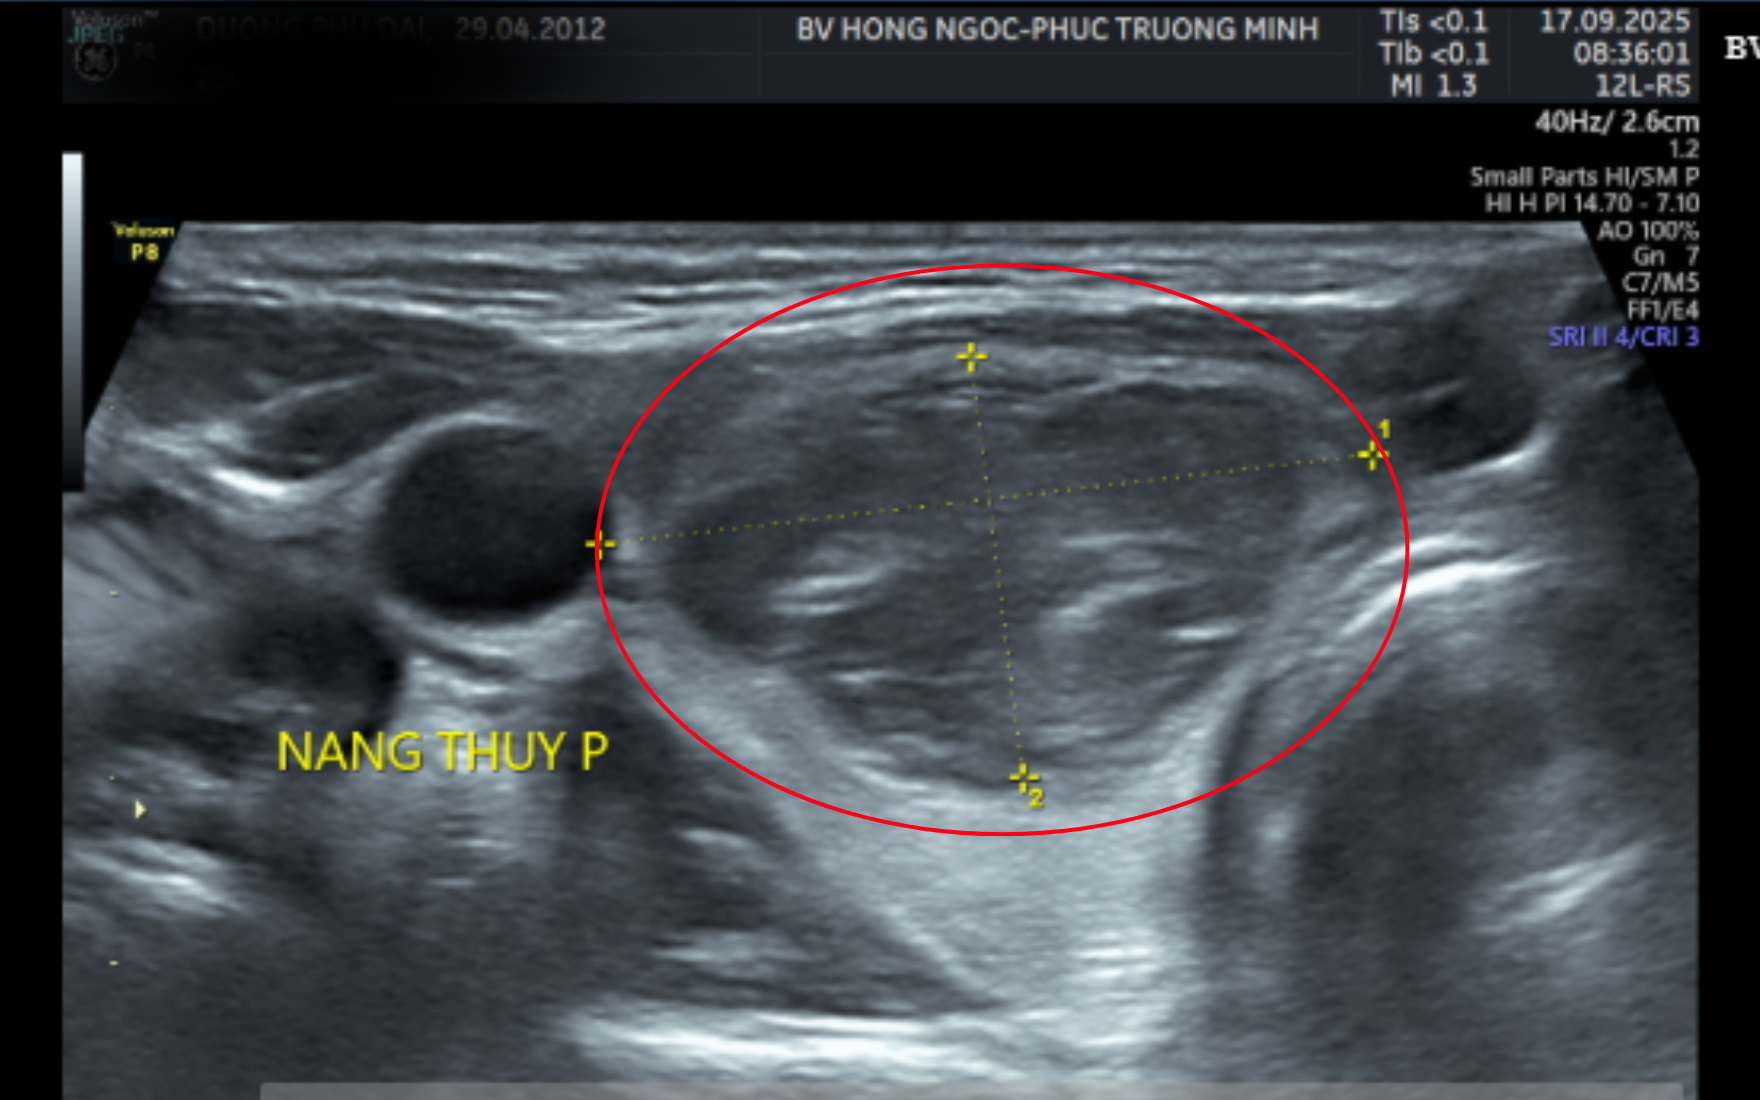

Thăm khám tại Bệnh viện Đa khoa Hồng Ngọc, kết quả siêu âm cho thấy bệnh nhi có khối u ở thùy phải tuyến giáp kích thước hơn 3 cm. Kết quả chọc hút tế bào bằng kim nhỏ (FNA) trước mổ cho thấy nghi ngờ ung thư tuyến giáp thể nhú nhóm V theo phân loại Bethesda.

Kết quả siêu âm cho thấy khối u lớn hơn 3cm